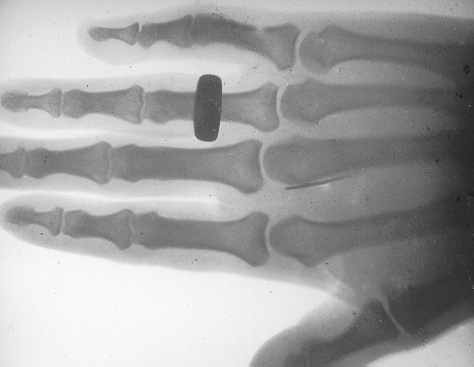

The newspaper report of the Röntgen ray experiments at the University aroused widespread interest among the members of the medical profession, so on Monday 1 June further experiments were conducted at the University in the presence of a large group of doctors and better results were obtained. While a 30-minute exposure to the rays gave a very clear picture of a foot encased in plaster of Paris produced a very clear picture, another experiment produced practical results. A lady who had been troubled by a piece of a needle lodged in her hand had the afflicted member subjected to the rays. Although doctors had not been able to locate the piece of needle, in the photograph it could be clearly seen at the base of her third finger and only a simple operation was needed to remove it. (see copy of the X-ray below).

Below: Lantern slide copy of the X-ray referred to in the above paragraph. The mask on the slide bears the hand-written inked inscription, "Needle in hand for 5 years 2/9/96" and also the wet-stamp impression, "W.T. ROWE." The exposure could have been from 5 to 10 minutes with Mr S. Barbour of F.H. Faulding operating the apparatus and Mr W.T. Rowe developing the plate.